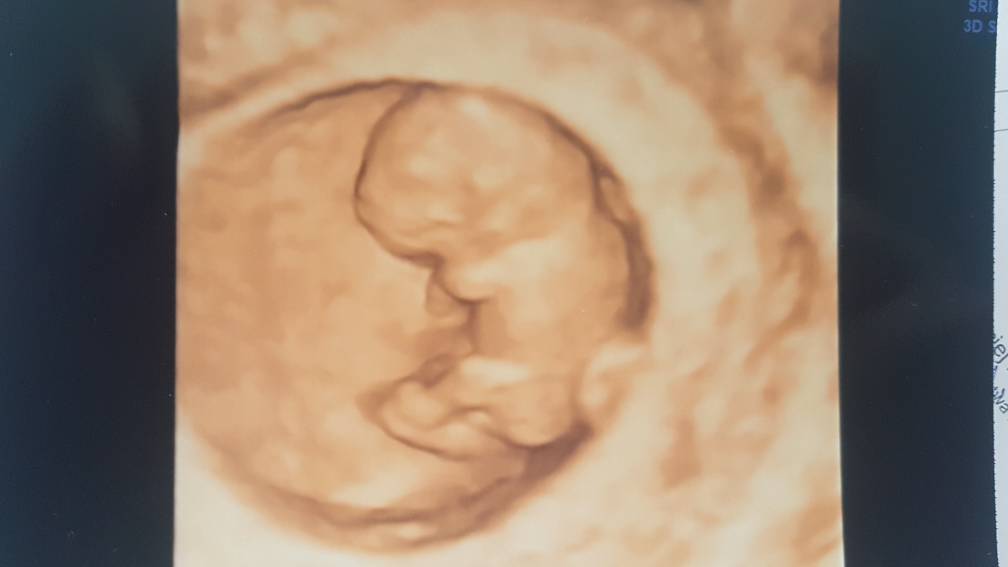

Ostatecznie zmieniłam lekarza i jestem mega zadowolona. Poprzedni podchodził do pacjentek powiedzmy że finansowo. Dzisiejsza wizyta zmieniła mój światopogląd o lekarzach. Za wizytę zapłaciłam tyle samo Ale trwała ona 45 minut. Lekarz dokładnie przeprowadził że mną wywiad, zapytał jak się czuje czy mam jakieś dolegliwości, jaka mam pracę. Przejrzał raz jeszcze wszystkie badania i kazał powtórzyć Toxoplazmoze. Przeprowadził dokładne badanie usg podczas którego wszystko objaśnia i wytłumaczył.

Czułam się komfortowo dopieszczona ( jako pacjentka) i uspokojona.

Bobas to chyba cały tata... wierci się niesamowicie [emoji16] ma 2, 49 cm -czyli jesteśmy w 9t1d. Tętno 169.

Badania prenatalne 16.10.

Poniżej zdjęcia maluszka